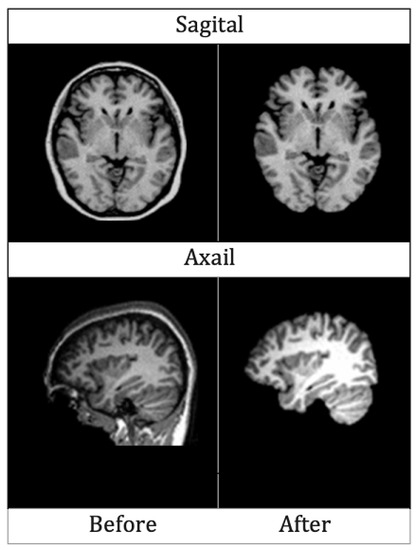

4.2.1. Skull Stripping

4.2.2. Segmentation

4.2.3. Normalization

4.2.4. Rescaling

4.2.5. Smoothing